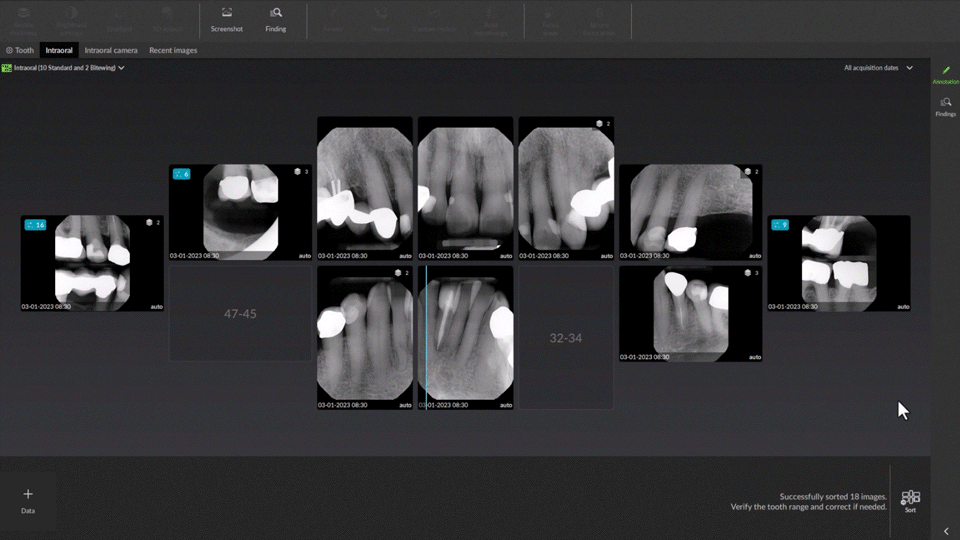

MagicSort™ – automatické rozpoznání čísla zubu pomocí AI

MagicSort automaticky rozpozná zachycené zuby na intraorálním rentgenovém snímku a přiřadí jim odpovídající čísla. Obraz se zároveň správně natočí a umístí na správnou pozici ve zvoleném radiografickém schématu. Tato funkce je součástí přiloženého softwaru DTX Studio Clinic.